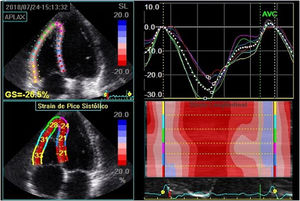

LV global systolic function was assessed by ejection fraction using the Simpson method in the apical windows of chambers four and two and peak systolic longitudinal strain two-dimensional speckle tracking echocardiography in the apical windows of chambers three, four and two, to obtain the LV global longitudinal strain (LVLSG). For image acquisition, image quality was optimized, with maximized frame rate (60-90 frames per second), minimized shortening, and the recording of at least three beats during apnea at the end of expiration. For LVLSG analysis, automated functional imaging (AFI) was used (Figure 1).

Global longitudinal strain calculation using two-dimensional speckle tracking, using AFI. In the figure, the global longitudinal strain of the left ventricle obtained was 23.5% in a patient with Type 1 diabetes.

GLPS_Avg: mean global longitudinal peak systolic strain; AVC: aortic valve closure time; HR: heart rate; AFI: automated imaging function.